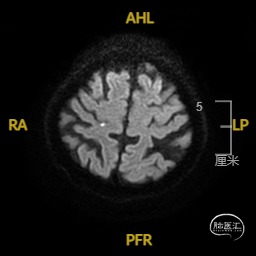

➢ 入院后头核磁检查

患者主因言语不利3天入院,头核磁提示右侧额、顶叶多发低灌注梗塞,脑血管造影提示右侧颈内动脉开口重度狭窄,为责任血管,另外患者前交通动脉、右侧后交通动脉开放不良,并且狭窄严重,考虑到高灌注风险,决定分期处理,一期小球囊扩张改善供血,二期支架成型。